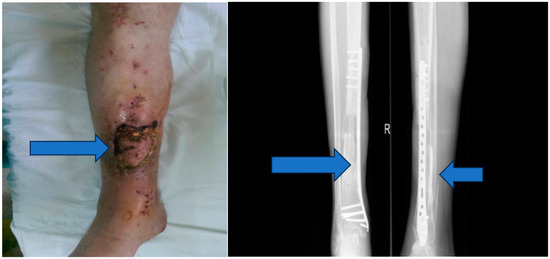

Stage 4: Flap integration and internal fixation (Figure 6).

Objective: To ensure the integration of the musculocutaneous flap and provide internal fixation to stabilize the tibia.

Methods: After an 8-week integration period, the musculocutaneous flap was deemed stable. The external fixator was removed, and internal fixation was achieved using a blocked Less Invasive Stabilization System (LISS) plate, which was inserted utilizing the Minimally Invasive Plate Osteosynthesis (MIPO) technique.

2.4. Clinical Assessment and Follow-Up

Throughout the treatment, the patient’s progress was closely monitored, and clinical signs of healing were recorded. Sterile cultures were obtained to verify the resolution of the infection. The patient’s overall condition, pain level, and functional status were assessed at regular intervals (Figure 7).

Figure 6. Musculocutaneous flap and internal fixation was achieved using a blocked Less Invasive Stabilization System (LISS) plate.

Figure 7. Six-month follow-up.